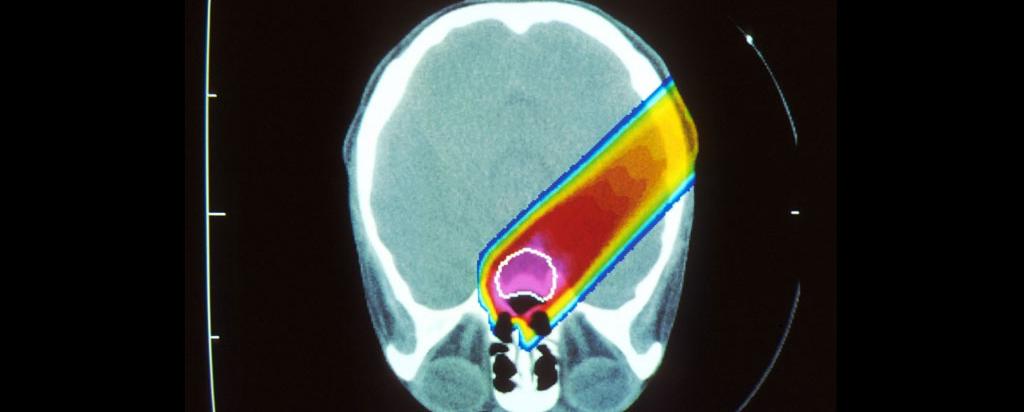

ANSTO is facilitating a national discussion on Australia's approach to particle therapy that also encompasses the emerging carbon ion- based techniques.

Many advanced nations (including Japan, Germany, Italy and Austria) also have carbon-ion particle therapy and international experience demonstrates that this can be both a cost effective and biologically effective shorter course of treatment for otherwise untreatable forms of cancer.